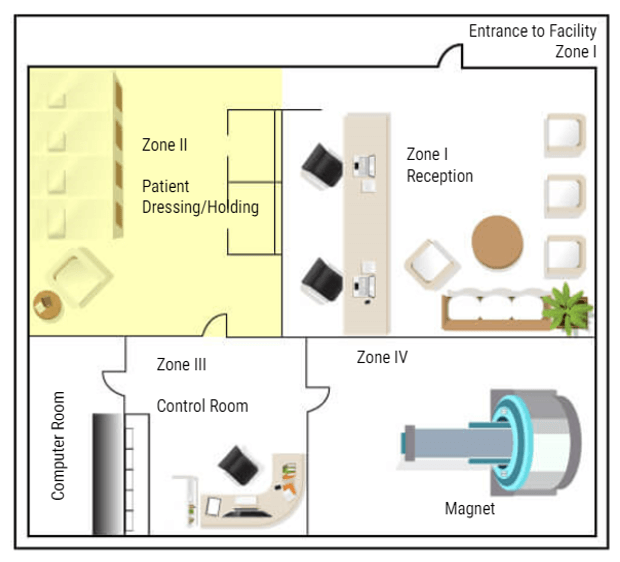

Now that we know what types of things to be concerned about in and around the MRI suite, we will now discuss MRI Zones and who can be in each zone.

Why Zones Are Important

In MRI we divide the work area into four zones. Each zone is very specific about who may enter and under what conditions. All zones must be marked in and around the MRI suite. There must also be a clear definition of where one zone ends and one begins, such as a doorway, chain/rope or another clearly visible sign. The signage should include who is allowed beyond that point. Let’s look at each zone:

Zone 1

Zone 1 is for the general public. Anyone can be in zone one. Some examples are hallways near the MRI area, the main waiting room, or a shared waiting area with other departments. There is NO screening needed to be in Zone One. While in zone one the patient may be asked to complete a screening sheet or be asked some basic safety questions before being moved to zone II.

Zone 2

Zone II is where a more thorough screening will take place. The patients will also be prepped for their scans in this area – changing clothes, removing all metal items and placing them in a safe place. Patients are only permitted to enter zone II when accompanied by a healthcare employee. Family members may also be permitted in Zone II accompanied by the healthcare worker without being screened. But this is the anyone not screened or cleared my go in the MRI area. ALL questions should be answered while the patient is in this area. Even if the patient has completed a screening form, they are not permitted beyond this point until they are cleared or accompanied by Trained MRI professionals.

Zone 3

The next zone is Zone three. This is the control area, where the MRI technologist would operate the scanner. Patients should be accompanied by an MRI safety trained individual to enter zone three. People who have not removed loose metals, or who have pacemakers or other unsafe medical devices, should not be permitted in zone III because of the proximity to zone IV. A screened but uncleared person may enter zone III ONLY under strict supervision by trained personnel, such as a patient who just wants to look at the MRI scanner to decide if they will be able to tolerate the exam.

Zone 4

The final zone is zone IV, the MRI scan room. ONLY CLEARED patients are permitted to enter Zone IV, accompanied by trained MRI personnel. The final step of clearance, while in zone III, should be to check the patient one last time for loose metals, other electronic devices and a last check of the critical screening questions. ACR suggests asking these questions a minimum of three times. Once At scheduling, once at screening and once at clearance. As an additional safety measure, many facilities build a metal detector into the doorway between Zone 3 and Zone 4. But there are hand-held devices that work well too and they are less expensive. Once the patient is cleared they can be taken into the MRI room and scanned.